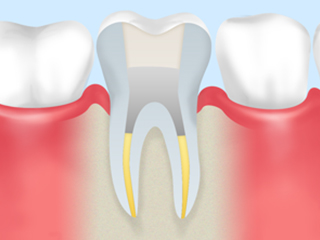

C3 虫歯の後期です。神経まで虫歯が進行しているので神経を取 る治療をし、歯の根の中を綺麗にしなければなりません。 今までの虫歯の状態に比べて治療の回数が増えます。 |

根管治療

歯の根の中は、中空になっていて、その中に神経や血管などが詰まっています。

虫歯などによって歯の神経に細菌が入り込んで炎症を起こすと、歯の神経は死んでしまいます。

深い虫歯などが原因で神経を取ったあと、根の中の中空部分をきれいにして処置をすることを根管治療と言います。